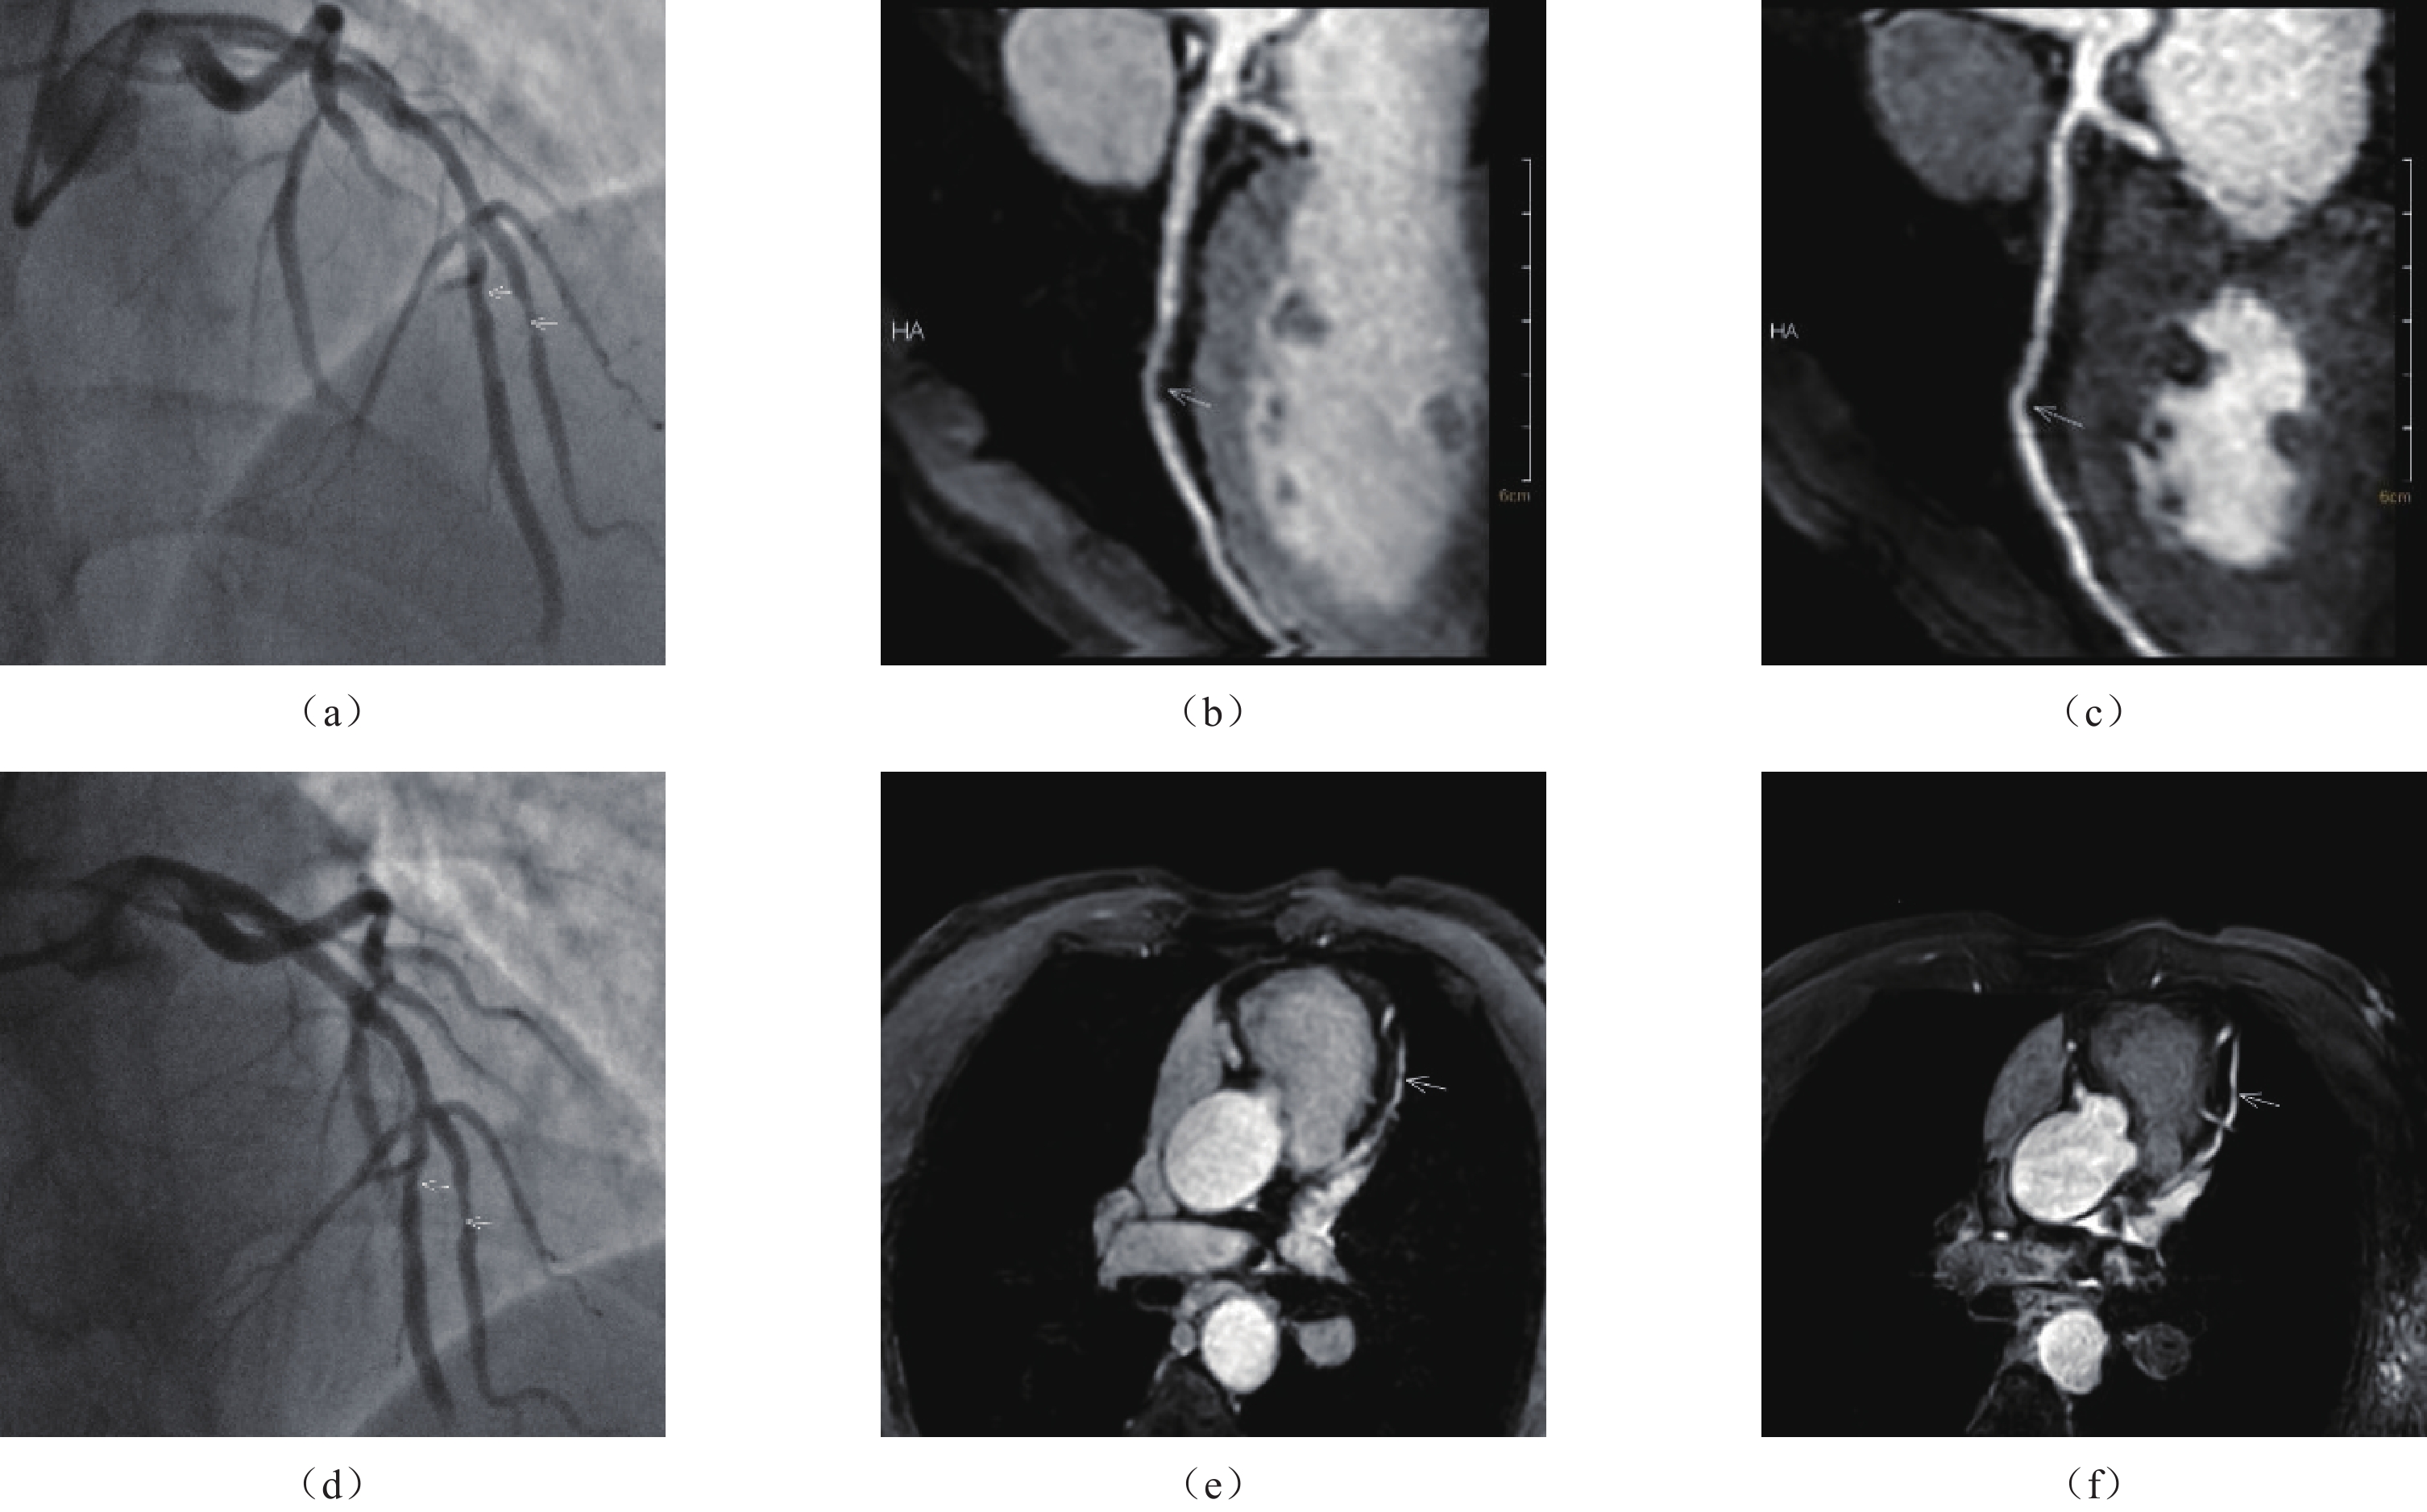

(85.6~91.9)同时,在基于血管水平,mDixon序列的F1值为91.3%,WHCA TFE序列使用SPIR技术为80.5%;在基于节段水平,mDixon序列的F1值为83.3%,WHCA TFE序列使用SPIR技术为71.9%。典型图像见图1。

![]() 图 1 冠状动脉造影(CAG)与全心CMRA多平面重组以及横断位图像对比图注:显示冠状动脉狭窄(↑),(a)(d)为CAG图像;(b)、(c)、(e)、(f)为CMRA图像;(a)(d)显示左前降支中段与第1对角支近段中度狭窄;(b)(c)分别为mDixon序列与WHCA TFE序列使用SPIR技术多平面重组图像第1对角支近段对应狭窄区域,mDixon序列可见中度狭窄,狭窄程度显示较TFE序列使用SPIR技术更加明显;(e)(f)分别为mDixon序列与WHCA TFE序列使用SPIR技术多平面重建图像左前降支中段对应狭窄区域。Figure 1. Comparison of coronary angiography (CAG) with whole-heart CMRA multiplanar recombination and cross-sectional images

图 1 冠状动脉造影(CAG)与全心CMRA多平面重组以及横断位图像对比图注:显示冠状动脉狭窄(↑),(a)(d)为CAG图像;(b)、(c)、(e)、(f)为CMRA图像;(a)(d)显示左前降支中段与第1对角支近段中度狭窄;(b)(c)分别为mDixon序列与WHCA TFE序列使用SPIR技术多平面重组图像第1对角支近段对应狭窄区域,mDixon序列可见中度狭窄,狭窄程度显示较TFE序列使用SPIR技术更加明显;(e)(f)分别为mDixon序列与WHCA TFE序列使用SPIR技术多平面重建图像左前降支中段对应狭窄区域。Figure 1. Comparison of coronary angiography (CAG) with whole-heart CMRA multiplanar recombination and cross-sectional images3. 讨论

图 1 冠状动脉造影(CAG)与全心CMRA多平面重组以及横断位图像对比图

注:显示冠状动脉狭窄(↑),(a)(d)为CAG图像;(b)、(c)、(e)、(f)为CMRA图像;(a)(d)显示左前降支中段与第1对角支近段中度狭窄;(b)(c)分别为mDixon序列与WHCA TFE序列使用SPIR技术多平面重组图像第1对角支近段对应狭窄区域,mDixon序列可见中度狭窄,狭窄程度显示较TFE序列使用SPIR技术更加明显;(e)(f)分别为mDixon序列与WHCA TFE序列使用SPIR技术多平面重建图像左前降支中段对应狭窄区域。

Figure 1. Comparison of coronary angiography (CAG) with whole-heart CMRA multiplanar recombination and cross-sectional images